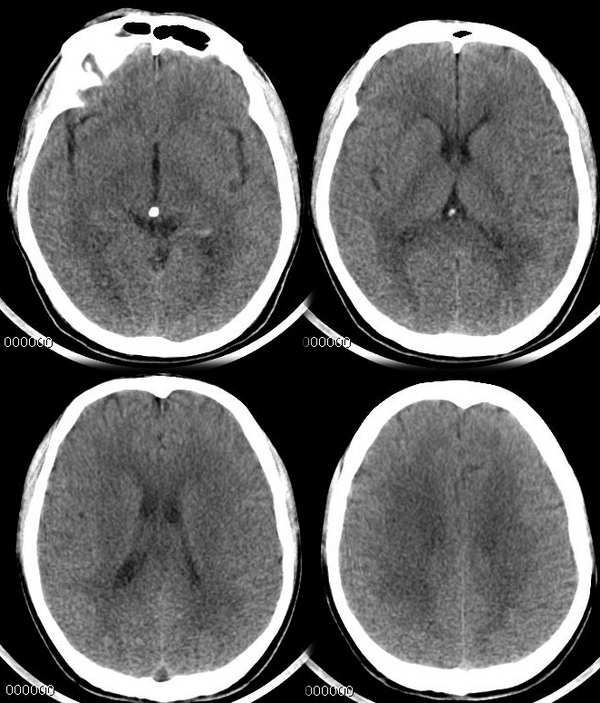

平扫空三角征最多见于蛛网膜下腔出血,多伴纵裂池改变。也可为贫血等原因所致。必要时增强扫描或mr排除静脉窦血栓。静脉窦血栓平扫多显示为高密度三角征或束带征。

1、左侧基底节及双侧放射冠区腔隙性脑梗塞;2、应该排除伪影所致的空三角征。